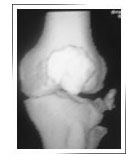

Before surgery 3-DCT